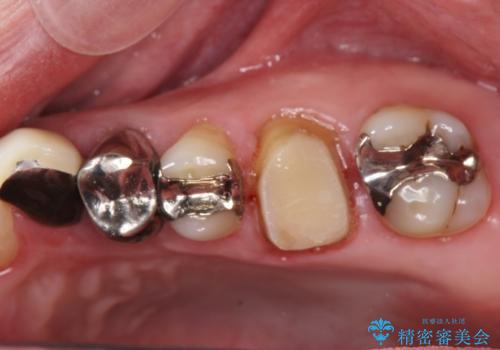

- 銀歯・虫歯・治療途中の歯を治していきたい、セラミックの歯にしたい!と希望され来院されました。

銀歯の下で再発した虫歯や、根尖病変等、多々の問題が認められましたがひとつづつ丁寧に改善し、長期的な予後の見込めるセラミック治療を行っていきます。